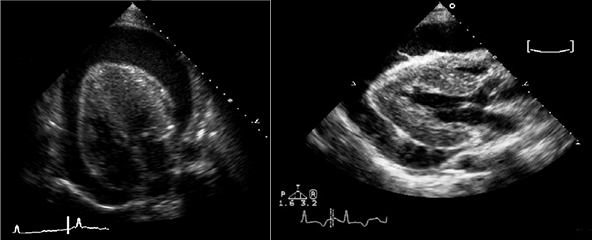

• Эхокардиография: выпот, утолщение перикарда.

• Выпот (>15–35 мл), сепарация эпикарда и перикарда >1 мм в диастолу.

• Величина выпота: малый (сепарация • Утолщение (>3–4 мм) и кальцификация перикарда (констриктивный перикардит).

• Эхокардиография: колебания сердца, выраженный выпот (>20 мм), диастолический коллапс камер сердца, аномальное движение МЖП, > вариабельности митрального потока (>25%) на вдохе.

• Выраженная сепарация эпикарда и перикарда >20 мм в диастолу на эхокардиограмме.

• Симптомный выпот более недели несмотря на лечение.